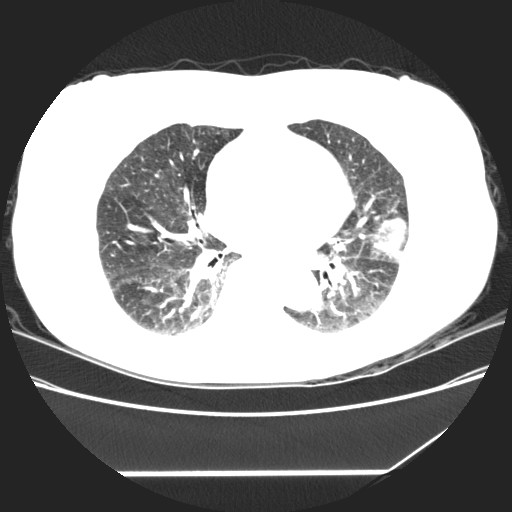

标题: CT24018:女性,62岁,咳嗽4年,无热,胸部CT扫 [打印本页]

女性,62岁,长期咳嗽,既往从事工作有粉尘接触,有高血压病史,110/150mmhg,近日咳嗽加重,脸面浮肿,请大家帮看下,

1、尘肺;2、慢性支气管炎合并肺部感染;3、心影增大(左房、左室大),考虑高血压性心脏病。

慢支并肺部炎症;右肺结核球?主肺动脉、右肺动脉影不宽,右心室不大,不支持肺心病;无心包积液。

间质性肺炎,有纤维化趋势。

1)慢性支气管炎并肺部感染、肺气肿。2)肺间质纤维化。

间质性肺炎,左下肺机化性肺炎。